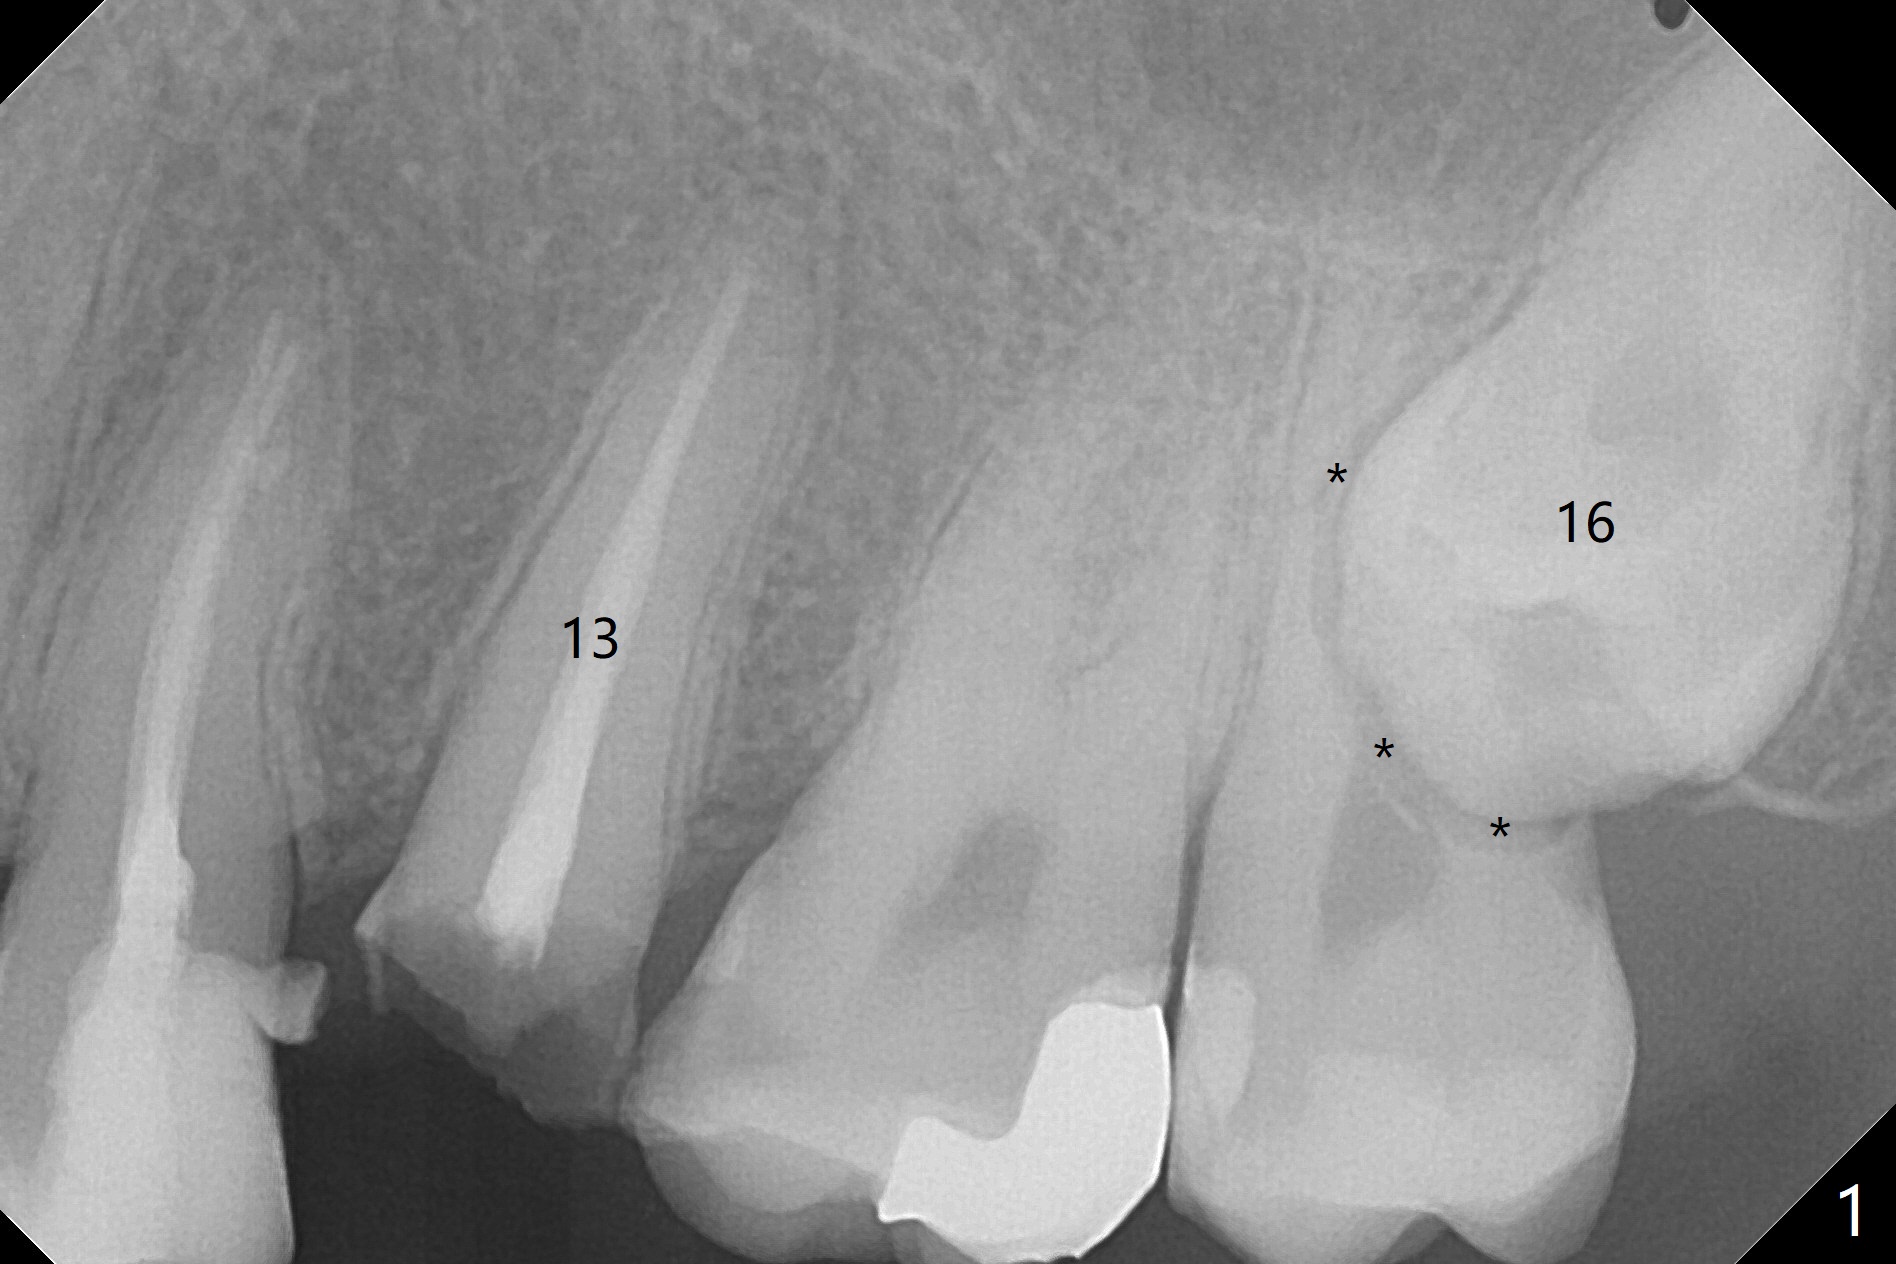

A 27-year-old man returns to clinic with #13 subgingival fracture, which is associated with Class III malocclusion and anterior open bite (Fig.1). Both #1 and 16 seem to be buccal to the 2nd molars, causing root resorption (Fig.1 *). Since the root of the 2nd premolar tilts distal, osteotomy for an implant will be in the mesiopalatal aspect of the extraction socket (Fig.2,3 red). Following implant placement, #16 will be extracted (Fig.3 black), laying foundation to distalize and intrude #14 and 15 to make space for #13 implant crown and reduce anterior open bite and posterior tooth overloading (Fig.4 arrow). No Deviation Clindamycin Xin Wei, DDS, PhD, MS 1st edition 08/25/2020, last revision 09/08/2020